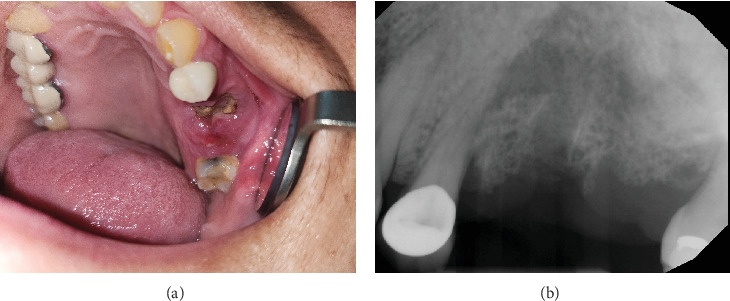

Medication-related osteonecrosis of the jaw (MRONJ) is a well-known side effect of bone-modifying agents such as antiresorptive medications including pamidronic and zoledronic acids (intravenous bisphosphonates) and denosumab (anti-RANK ligand humanized monoclonal antibody). The major risk factor for the precipitation of MRONJ in a patient taking antiresorptive medication is dentoalveolar trauma such as dental extractions. Management of MRONJ in oncology patients is exceptionally challenging. In this report, two multiple myeloma patients with longstanding advanced-stage MRONJ were successfully managed with combined pentoxifylline-tocopherol treatment pre- and postextraction/sequestrectomy. In conclusion, based on this report and other published reports, it appears that the use of combined pentoxifylline-tocopherol protocol in the management of MRONJ is effective.